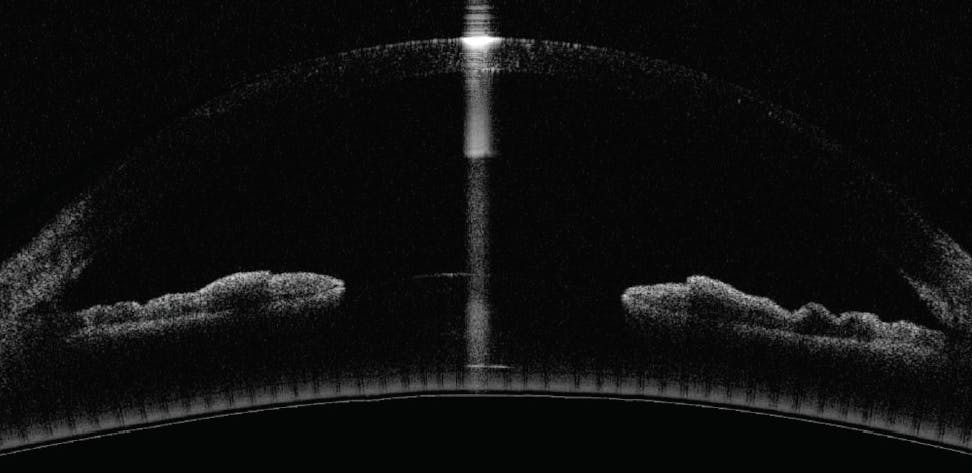

Figure 3. OCT imaging of the optic nerves showed significant retinal nerve fiber layer loss superiorly and inferiorly in each eye.